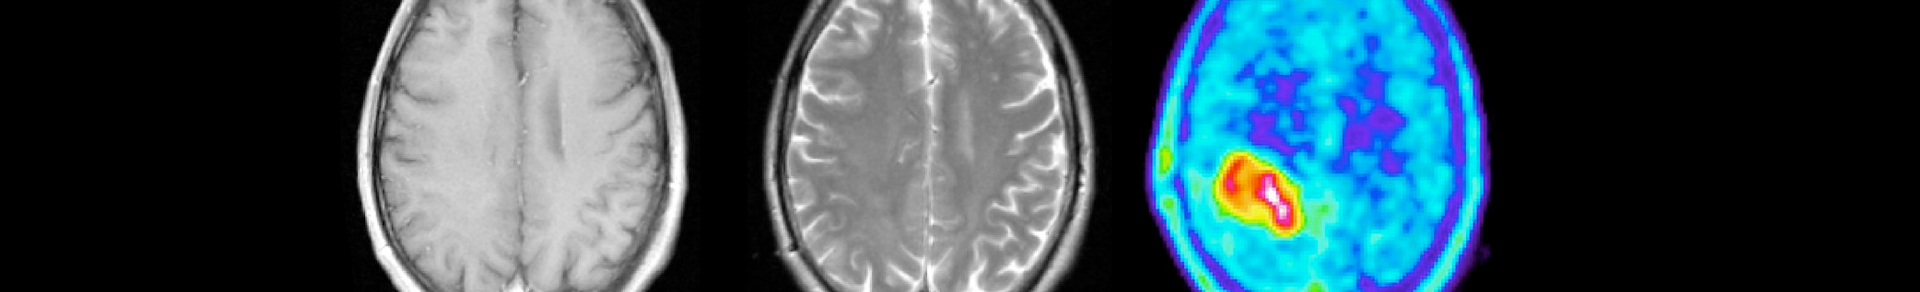

For the diagnosis and treatment of a brain tumour, it is important to determine the exact size and volume in order to be able to check whether the tumour is responding to treatment or whether it is continuing to grow. Clinics often use magnetic resonance imaging (MRI) for this, which specifically records structural changes in the tissue. However, these do not necessarily reflect the actual extent of the tumour. Another imaging procedure records the altered metabolism of the cancer cells and often provides results that differ from MRI: amino acid positron emission tomography (PET).

PET uses radioactively labelled biomolecules to make metabolic processes visible. Amino acids have proven particularly useful for the imaging of brain tumours. The rapidly growing cancer cells take up the amino acids much faster than the healthy brain cells. Based on the enriched amino acids, the PET images can be used to determine the location and size of the metabolically active tumour.

Researchers from Jülich, Heidelberg and Cologne have developed a deep learning algorithm called JuST_BrainPET* that automatically recognizes brain tumours on PET scans and determines their volume. The team used 699 PET scans from 555 brain tumour patients for this purpose. The AI results agree very well with the values that experts determine from PET scans. Plus: the AI only needs a few minutes to do this.